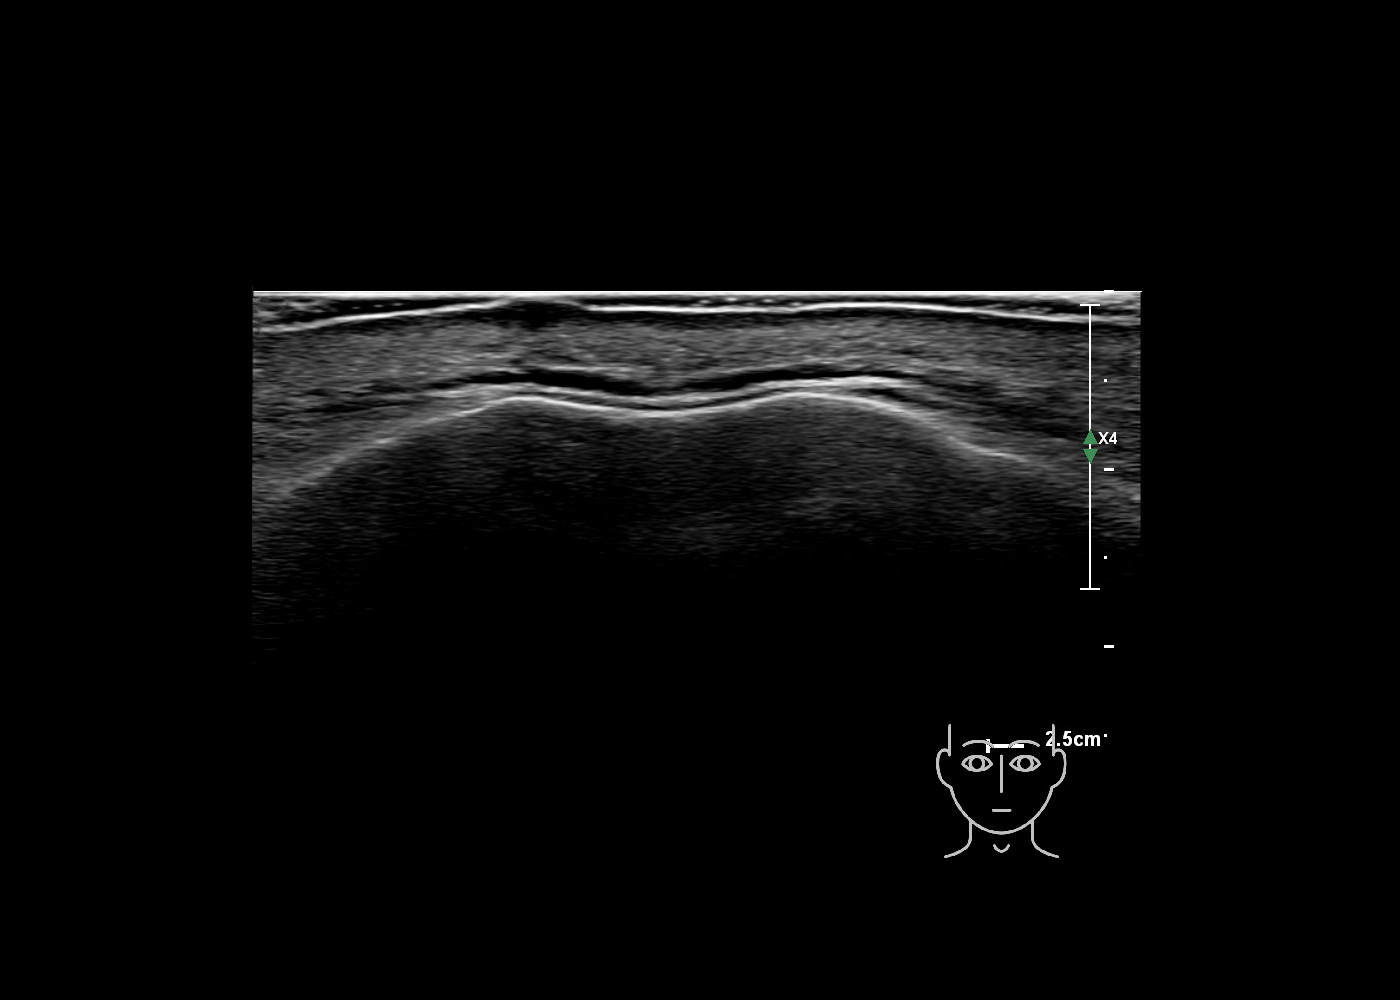

In this section you will learn more about the different layers of the face with the use of ultrasound. When you click on the secondary ultrasound image, you will see the different structures as an overlay. This will help to train yourself to recognize the different layers of the face.

Study the first image to recognize the different layers. If you are sure about the layers, swipe to the second image to view the answer (if applicable).